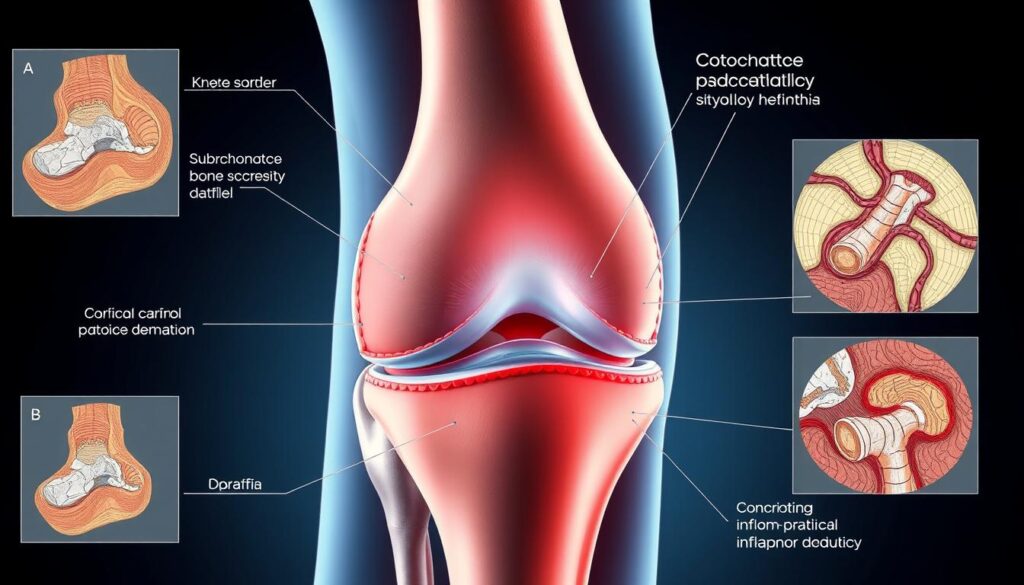

Arthrose stellt eine komplexe Gelenkerkrankung dar, die durch fortschreitenden Knorpelverlust charakterisiert ist. Diese degenerative Erkrankung entwickelt sich über Jahre hinweg und beeinträchtigt die Lebensqualität der Betroffenen erheblich. Um innovative Behandlungsmethoden wie die Stammzellentherapie zu verstehen, ist es wichtig, die Grundlagen der Arthrose zu kennen.

Arthrose entsteht, wenn der schützende Knorpel in den Gelenken abgebaut wird. Dieser Knorpelverlust führt dazu, dass die Knochen direkt aufeinander reiben. Die Folge sind Entzündungen und strukturelle Veränderungen im gesamten Gelenk.

Typische Symptome zeigen sich als Anlaufschmerzen am Morgen oder nach längeren Ruhephasen. Belastungsschmerzen treten bei körperlicher Aktivität auf. Viele Patienten berichten über Schwellungen und knirschende Geräusche bei Gelenkbewegungen.